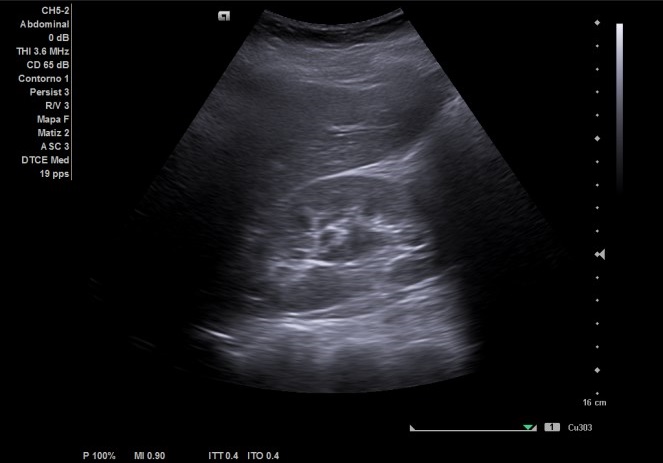

Riñón derecho ligeramente aumentado de tamaño con aparente hidronefrosis grado 1-2.

Riñón izquierdo tamaño y ecoestructura normal. Se visualiza vejiga con paredes homogéneas y ambos jets. Útero en anteversión, con mioma de 15,14 x 9,98 cm. Anejos normales.